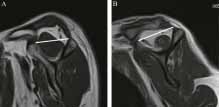

Μαγνητική τομογραφία

Είναι σηματική για την αξιολόγηση της ποιότητας του υπερακανθίου μυος, ενδεικτική για το μέγεθος το σχήμα και το βαθμό της ρήξης ή συρρίκνωσης του τένοντα, αλλά και στην αξιολόγηση της μυικής ατροφίας του υπερακανθίου σε οβελιαία προβολή. ( tangent sign εικ)